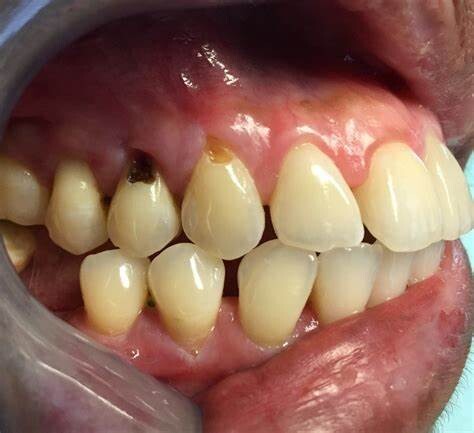

Causes of Gumline Cavities

A dental cavity forms when plaque, a sticky bacterial film that builds up inside the mouth, solidifies and creates an area of decay. This bacteria combines with sugar to produce acids that dissolve the tooth's enamel, the hard surface that works as a protective layer against tooth decay. And when this protective layer begins to wear, different types of cavities have the potential to form.

Have you ever wondered what areas of the mouth are most prone to tooth decay? Well, not all teeth are created equal. Plaque tends to accumulate more easily in certain areas. For example, the back teeth' pits and fissures (molars) are a hot spot for plaque and the spaces in between the teeth. Plaque also builds up easily along the gumline, and when this plaque isn't removed, a gumline cavity can form.

Gumline cavities can also be associated with exposed tooth roots. Gum tissue usually protects the roots, but the roots will be vulnerable if the gum tissue recedes. That's because roots are covered in a material called cementum, which is much weaker than tooth enamel.

Tooth decay – Without the protective covering of gum tissue, exposed tooth roots become much more vulnerable to invasion by decay-causing oral bacteria. Plaque and tartar can readily adhere in these areas, leading to cavities.

Root cavities – Once gum recession occurs, cavities at the gumline and beneath the gums can form. These subsurface lesions are more difficult to detect, treat, and restore.